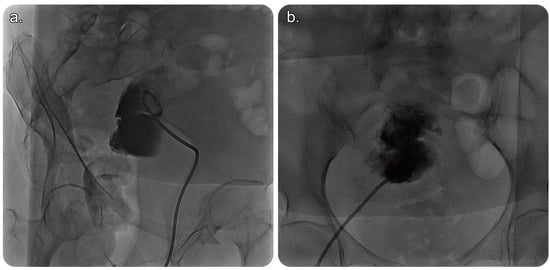

CT of the abdomen and pelvis with intravenous (IV) contrast revealed a sizable endometrial cavity collection with air foci, faint fluid–fluid levelling, and irregular endometrial enhancement. Moreover, an enhanced cervical lesion was identified (Figure 1). Her laboratory results indicated a slight increase in white blood cell count; however, other test results were within the normal range. Pap smear and human papillomavirus tests indicated no evidence of malignancy.

Figure 1. Reformatted computed tomography (CT) images of the abdomen and pelvis with (intravenous) IV contrast. (a) Axial cut CT of the pelvis showing an endometrial fluid collection with air focus at the non-dependent part of the endometrium. The endometrial lining shows an evident contrast enhancement. No CT evidence of anterior abdominal scar is seen, proving no prior history of Caesarean birth. (b) Coronal and (c) sagittal CT of the abdomen and pelvis showing endometrial fluid collection with an air focus at the non-dependent part of the endometrium.

It is performed using ultrasound, fluoroscopy, and/or cross-sectional imaging guidance. Ultrasound guidance is the preferred modality, wherein CT is implemented in cases with deep collections, difficult access, or lesions that cannot be visualised using an ultrasound scan [2] (Figure 1 and Figure 2).